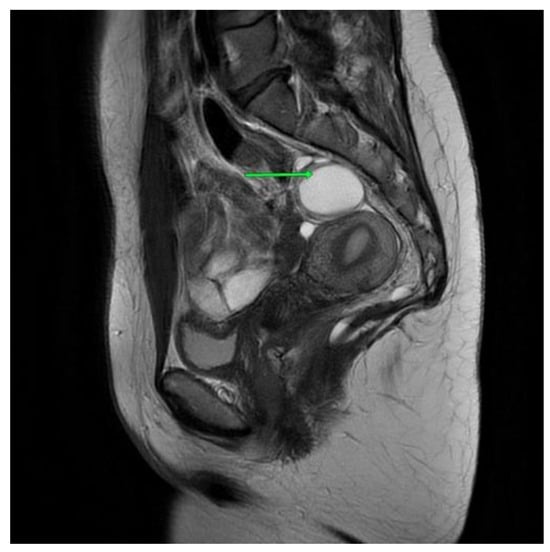

The first patient is a 40-year-old woman with large intestinal hyperplastic polyps and hemorrhoids. The pelvis minor tumor was diagnosed in 2016 during a routine ultrasound, and the patient underwent an unsuccessful surgery the same year. The tumor was asymptomatic, but in 2021, the patient started to experience morning tenesmus, urinary outflow disorders and painful ovulation. The physical examination showed left-sided thickness in a per vaginam examination. An MRI scan the with contrast of the lesser pelvis revealed a cystic, multilocular mass measuring 8.9 cm × 8.1 cm× 6.3 cm. This lesion shifted the rectum forward and to the left. It pressured the reproductive organ. The MRI scan aroused suspicion of a tailgut cyst [Figure 1].

Figure 1. First patient MRI scan of the lesser pelvis. Green arrow shows the lesion.